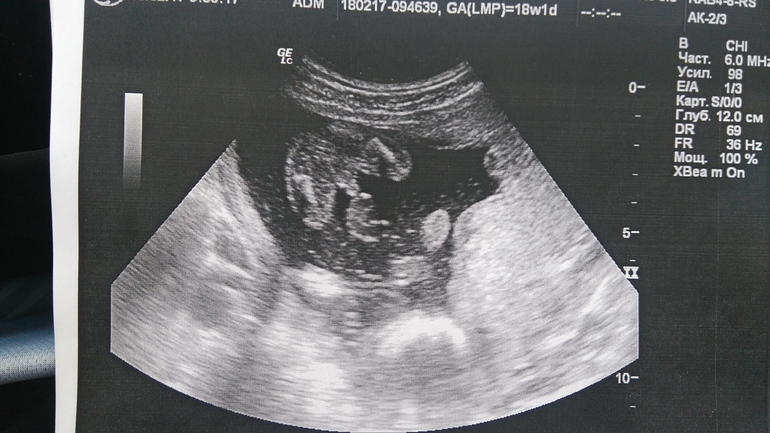

Из-за того, что малыш так низко лежит, нормального общего снимка не получилось:

Я так понимаю, что головка внизу справа и рядом правая ручка.